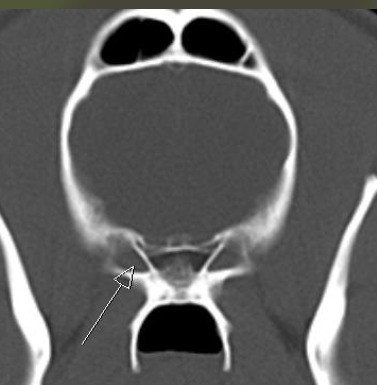

A dorsum sella B oval foramen